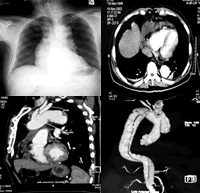

患者于入院后第10日行胸腹部增强CT(图2~4)发现,主动脉夹层自升主动脉至肾动脉水平广泛撕裂(DebakeyⅠ型),升主动脉血肿。患者立即被转入心外科病房,于入院后第12日行升主动脉及部分主动脉弓置换术,手术顺利,术中见主动脉夹层破裂导致心包内大量陈旧性血块,主动脉假腔内大量机化血栓,假腔破口在右无名动脉和左颈总动脉开口之间。患者术后恢复良好,体温降至正常。

图1 胸片可见纵隔增宽、心影增大

图2 胸部增强CT可见降主动脉夹层形成、心包积液

图3 增强CT矢状面可见升主动脉严重迂曲,夹层形成

图4 CT重建后可见升主动脉至肾动脉水平广泛夹层形成, 百拇医药